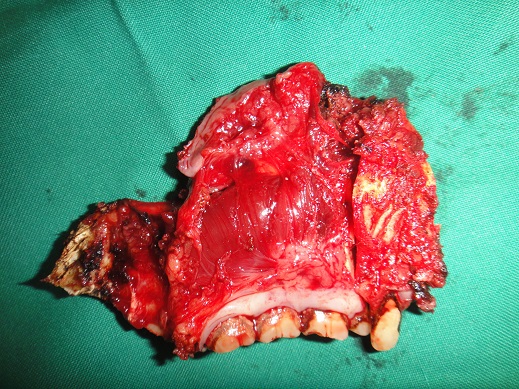

32 YEARS OLD MALE SUFFERING FROM RIGHT LOWER GINGIVO BUCCAL MUCOSA CARCINOMA INVOLVING RIGHT RETROMOLAR TRIGONE.PATIENT HAS ACTIVE PULMONARY TUBERCULOSIS.RIGHT RADICAL NECK DISSECTION WITH RIGHT DISTAL MANDIBULECTOMY WITH RIGHT LOWER ALVEOLECTOMY WITH RIGHT PECTORALIS MAJOR MYOCUTANEOUS FLAPE DONE.

31-12-2021